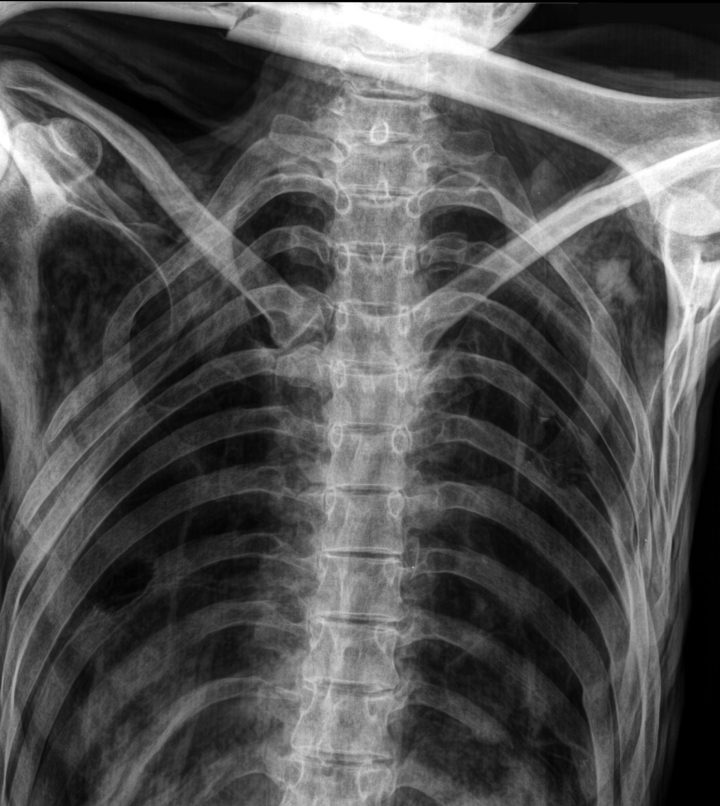

Esame radiologico con il nuovo apparecchio per la tomografia computerizzata (CT)

Nel 2013 i radiologi altoatesini Paul Gostner e Patrizia Pernter hanno realizzato una nuova tomografia computerizzata dell’Uomo venuto dal ghiaccio all’ospedale di Bolzano. Per questo esame hanno utilizzato un apparecchio CT di nuova generazione che, grazie a un’ampia apertura, ha permesso ai medici di scannerizzare Ötzi completamente dalla testa ai piedi, nonostante la posizione delle sue braccia. Oltre alla già nota arteriosclerosi, che interessava le arterie dell’addome e delle gambe, grazie alla migliore qualità delle immagini i due medici hanno evidenziato per la prima volta tre piccole calcificazioni in prossimità del tratto di efflusso cardiaco. Questa scoperta conferma la validità dei risultati ottenuti dai microbiologi di EURAC Research ovvero la presenza di una forte predisposizione genetica allo sviluppo di malattie cardiocircolatorie, da identificare come principale causa della sua arteriosclerosi.